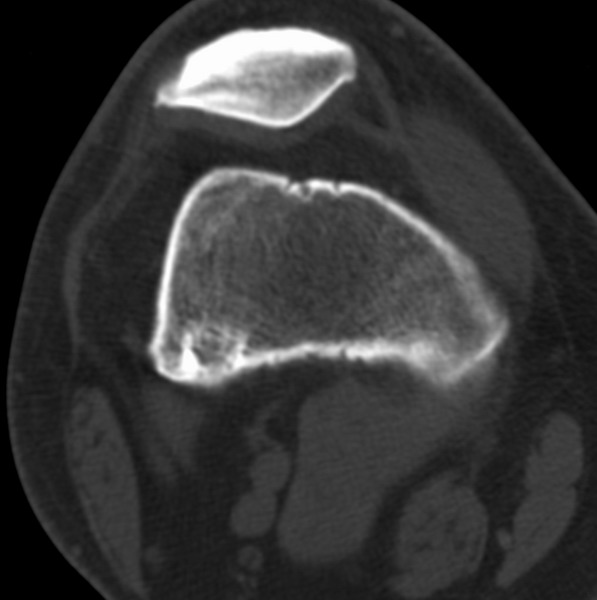

标题: CT21959:骨肿瘤请会诊。

右侧膝关节疼痛一月

男、48

股骨下段、胫骨上段。

1、股骨干骺端病变考虑干骺端纤维性皮质缺损愈后(非骨化性纤维瘤)改变,胫骨近端内生骨瘤(或干骺端纤维性皮质缺损愈后改变);

2、骨关节炎,骨质增生,股骨外侧髁退变性囊肿(关节面软骨下囊肿);

3、髌骨前缘裂纹骨折?